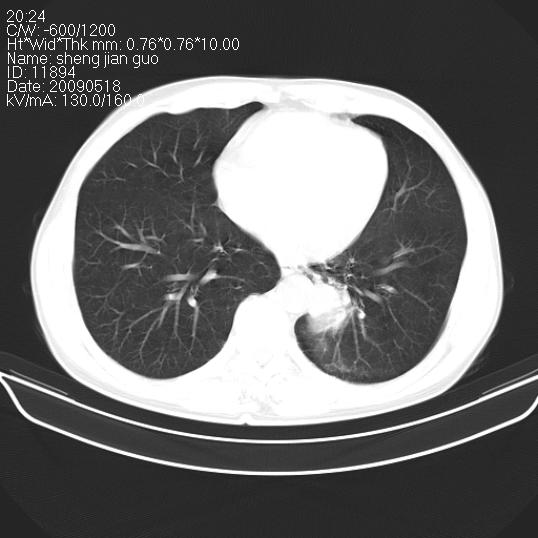

以下是引用zjzjr在2009-5-19 17:25:00的发言:[br]支持楼主考虑,另左肺下叶阻塞性炎症。

以下是引用zhao_bin2008在2009-5-19 17:48:00的发言:[br]支持左肺下叶周围型肺癌并阻塞性肺炎。

以下是引用杀毒软件在2009-5-19 17:36:00的发言:[br]支持楼主

以下是引用zsl6918在2009-5-20 7:10:00的发言:[br]左侧中心型肺癌!